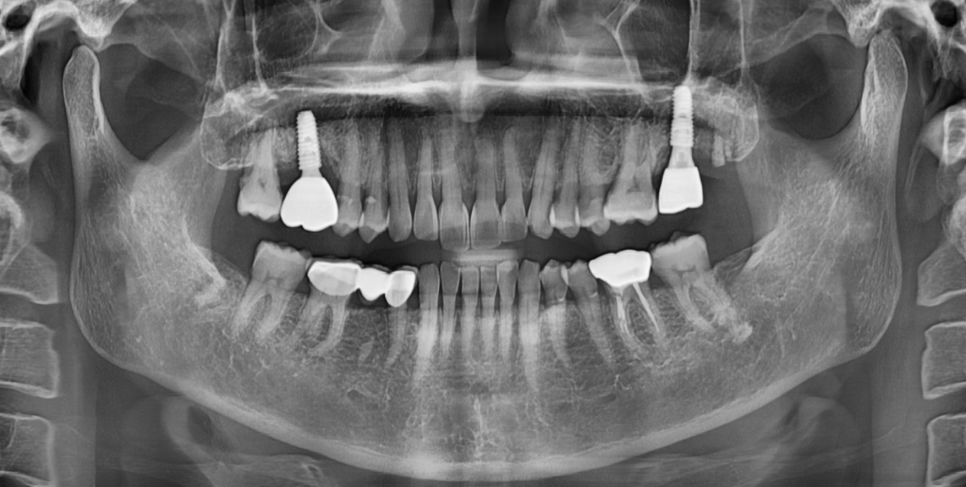

250724 x-ray를 찍어 보철이 매끄럽게 들어갔나 확인도 해보고요

임플란트의 보철의 높이나 형태를 미세하게 다듬으면

대부분 증상이 개선됩니다.

그럼에도 계속해서 볼을 씹으신다면

보철을 재제작하는 방향이 있습니다.

크기를 줄인다거나

볼살이 덜 걸리도록 형성해주는 것이죠.